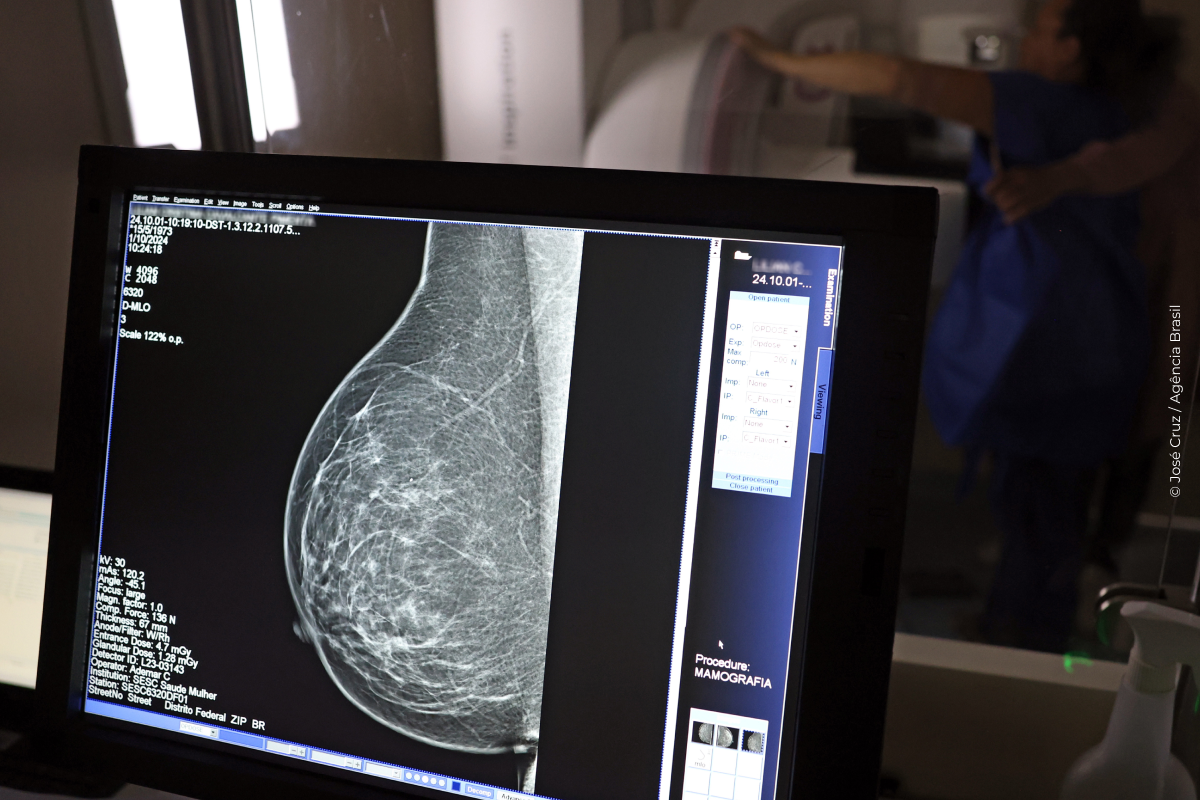

Falta de acesso a mamógrafos limita prevenção do câncer de mama

No mês de conscientização sobre o câncer de mama, um relatório destaca a importância de acesso igualitário ao rastreamento e tratamento da doença. Segundo o Atlas da Radiologia no Brasil, do Colégio Brasileiro de Radiologia e Diagnóstico por Imagem (CBR), o acesso aos mamógrafos ainda é um desafio.

O país tem 6.826 equipamentos registrados, sendo 96% em funcionamento. Metade deles está disponível no Sistema Único de Saúde (SUS), responsável por atender 75% da população. Isso equivale a 2,13 mamógrafos por 100 mil habitantes dependentes do SUS.